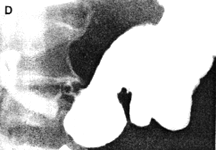

Case 29.4 F.F., 29 year old female, presented with epigastric pain and loss of weight. Radiographic examination showed an ulcer 1.5 cm in diameter on the lesser curvature of the stomach at the incisura angularis (Fig. 29.4 (A-D). A cylindrical contraction, 3.0 cm in length and containing a longitudinal mucosal fold, was seen in the pyloric region; a prominent pseudo-diverticulum was evident on the greater curvature side of the contraction, the appearances tallying with contraction of the pyloric sphincteric cylinder. Occasionally a minor degree of relaxation occurred, but most of the time the contraction remained as illustrated, with absence of normal cyclical activity. (Fig. 29.4 A-D). Response to anti-ulcer therapy was poor. Endoscopic biopsy 6 months later showed an ulcer at the angulus with surrounding induration. Microscopically the base of the ulcer consisted of fibrinopurulent material, fibrotic tissue and well-differentiated adenocarcinoma cells. Billroth II partial gastrectomy confirmed the large ulcer with indurated edges on the lesser curvature. Microscopically a well- differentiated adenocarcinoma, infiltrating locally through the muscularis externa into the subserosal tissue, was seen. The adjacent gastric mucosa showed areas of intestinal metaplasia. Microscopic examination of l7 lymph nodes revealed no carcinoma cells. It was concluded that the appearance of a chronic ulcer with dense fibro-collagenous tissue and carcinoma cells in the base, was compatible with so-called "ulcer cancer", i.e. carcinoma originating in a chronic gastric ulcer.

| Fig. 29.4 A-D Case F.F. Malignant ulcer at incisura angularis (open arrow). Constant contraction of pyloric sphincteric cylinder with absent cyclical activity (filled arrows) | |